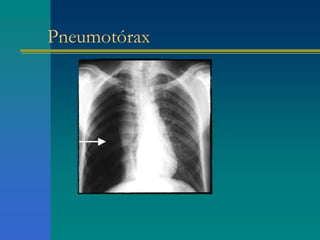

Pneumotórax  expansi-

 FTV timpânico  MV

Pneumotórax Voz distante

Principais síndromes respiratórias InspeçãoPalpação Percussão Ausculta Condensação pulmonar  expansi- bilidade  FTV maciço  MV Pneumotórax  expansi- bilidade  FTV timpânico  MV Derrame pleural  expansi- bilidade  FTV maciço  MV Atelectasia pulmonar  expansi- bilidade  FTV maciço  MV

A ausculta davoz no exame pulmonar Normal D>E Ápice > base Condensação pulmonar E>D ou Broncofonia - sílabas perceptíveis Pneumotórax Voz distante Derrame pleural Egofonia – no limite superior voz caprina Atelectasia pulmonar Voz distante (brônquio ocluído)